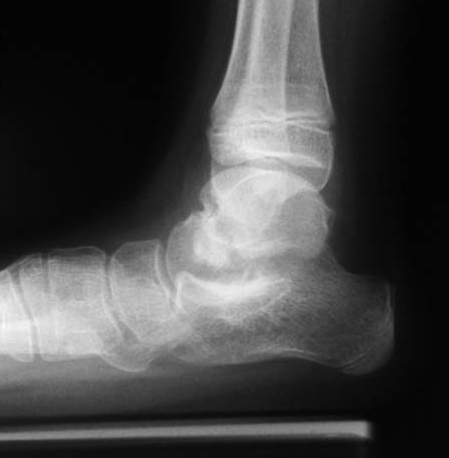

Röntgen Fuß AP und seitlich im Stand oder belastungssimuliert (Abb.1,2).

• Röntgen des dargestellten Falles 3 Monate post OP (Bild 25,26)